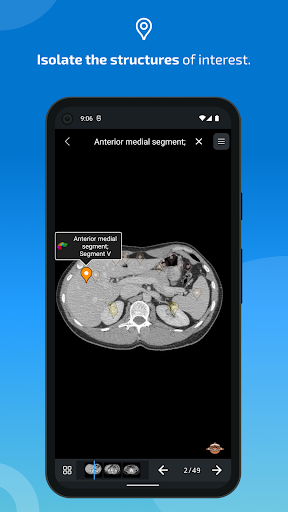

- Ketuk label untuk menampilkan struktur anatomi

-Dalam tampilan detail struktur anatomi , pin sekarang menunjukkan struktur terkait di semua gambar yang ada